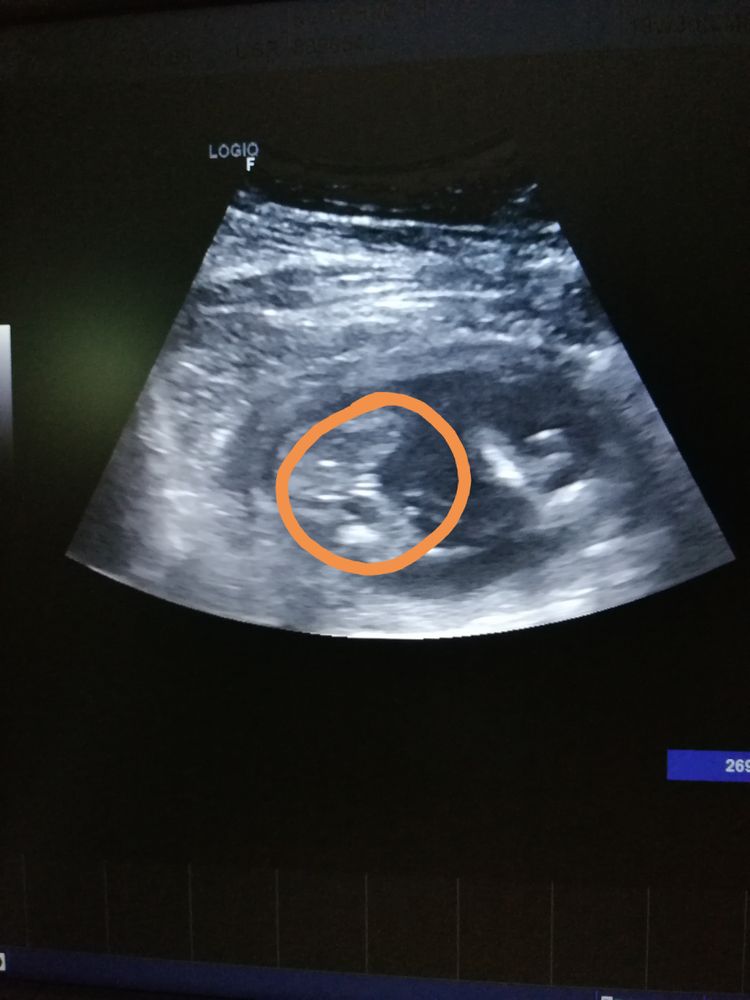

Мама мальчика или все таки девочки?

Мне в 12 недель сказали что половой бугорок как у мальчишки, в 16 недель в точности как у вас на фото все было , я ещё и в интернете смотрела везде пирожочек такой- сказали что девочка.В итоге в 21 пошла и все выросло 🤣🤣🤣🤣мальчик , хотя в 16 не было писюна!Так что точно вам скажут на втором скрининге!Я не думала что за месяц так все изменится- но картинка реально поменялась.Я кстати врач -не гинеколог конечно, но в картинках и узи разбираюсь , и в свои 16 я видела девочку, а в 21 оказалось мальчик!

девочка помоему

Девочка))) у нас такая же фоточкк есть.

Узнаю наше узи, вероятно, что все-таки девочка 😍

Там по наклону полового бугорка определяют, нет там ещё подовых губ!

Matimacheha, в 18 недель уже половые органы видны. Почитайте в интернете)

Matimacheha, половой бугорок - это в 11-13 недель, а дальше уже формируются гениталии.

Реально на девочку похоже 😍

Я бы сказала, что это девочка, у мальчика совсем по другому уже видно.

Мальчик или девочка?😉 Беременность третья, а ничего не меняется. Давайте разглядывать половой бугорок, девочки!)